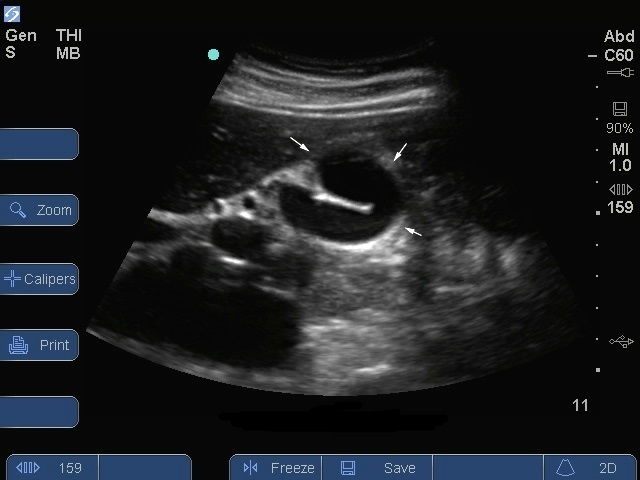

胆嚢 3 画像

S シリーズ: 胆嚢縦断面咽頭キャップ。